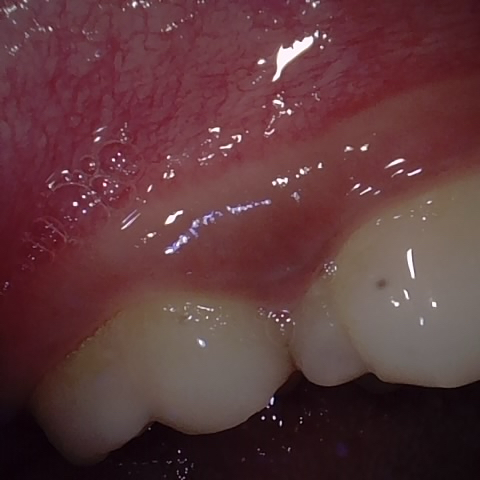

Annotated as "Good"